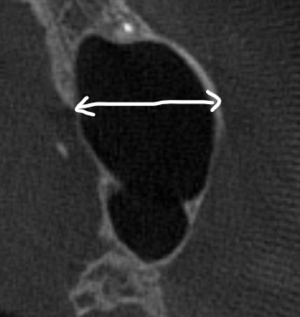

根管充填が不十分で、すき間もあり不良である

すき間なく緊密に根管充填されている

再感染リスクを抑える垂直加圧方式で充填しています(すき間が生じにくい)